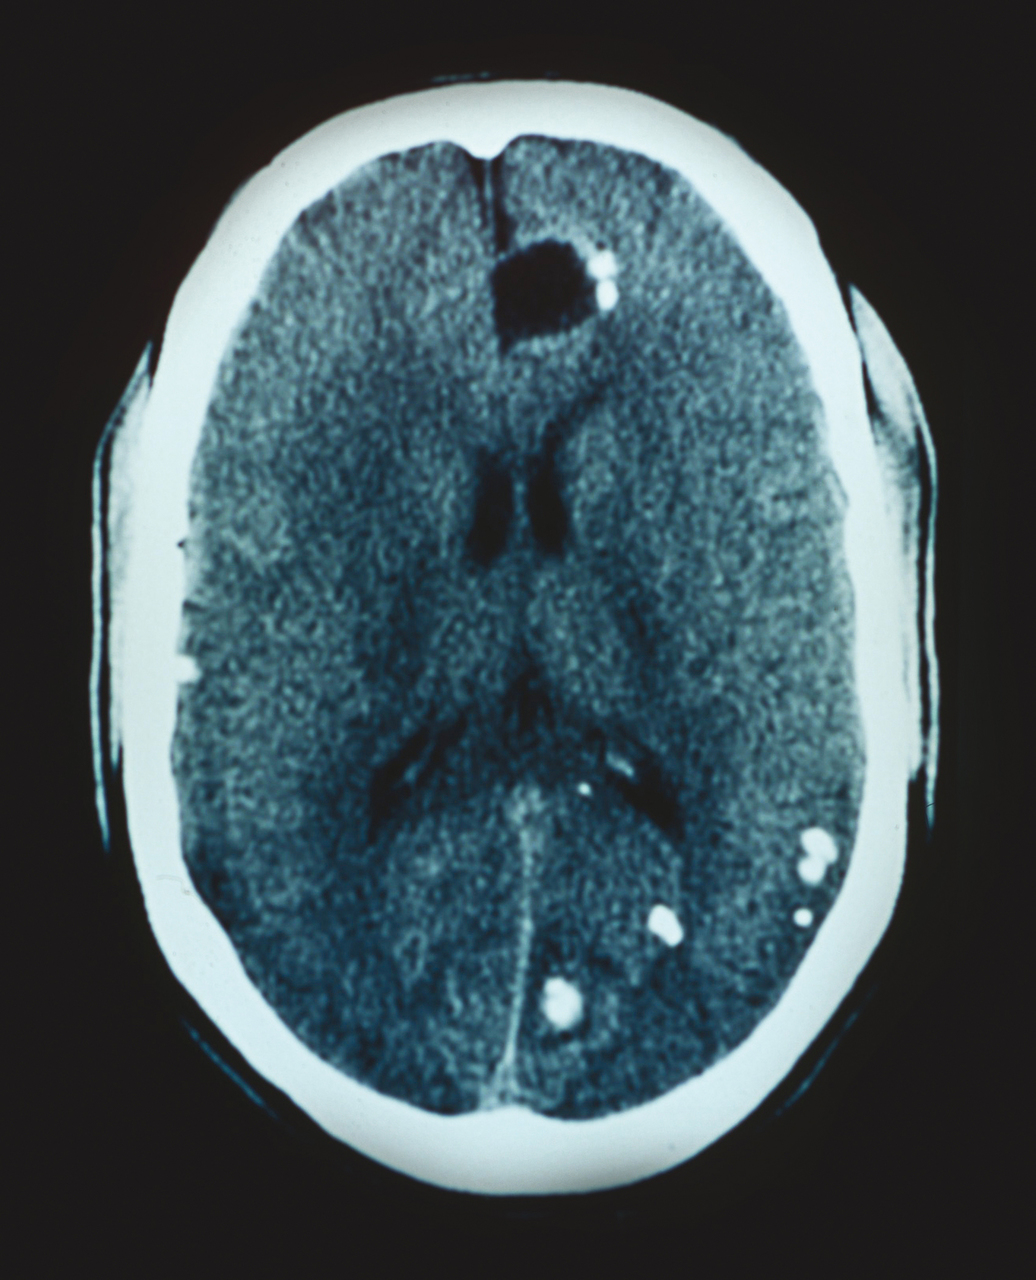

Il s'agit d'une neurocysticercose. La tomodensitométrie cérébrale révèle des images caractéristiques : images calcifiées et lacunes hypodenses. Le sérodiagnostic du Taenia du porc ou Solium est positif en ce cas. Les larves de Taenia Solium, libérées par les sucs gastriques, traversent la paroi digestive et passent dans la circulation pour former des kystes dans les muscles, l'œil et le cerveau (neurocysticercose), pouvant être responsable de convulsions. Les kystes entraînent d'abord une réaction granulomateuse puis se calcifient, et les symptômes dépendent essentiellement de leur localisation. Au cours de la neurocysticercose, toute la symptomatologie neurologique est possible, en fonction des localisations, des rapports anatomiques et du nombre de lésions. À La Réunion, la cysticercose est considérée comme la première cause d'épilepsie. La prévention impose la consommation de viande cuite ou congelée (de façon industrielle, les congélateurs familiaux ne permettant pas d'atteindre la température nécessaire), la surveillance vétérinaire des abattoirs, et la lutte contre le péril fécal.